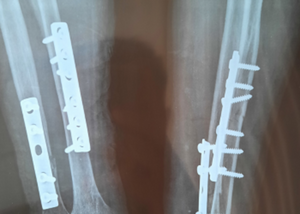

Fracture and Trauma Care

Fracture Treatment in Lucknow | Early Care, Healing & Modern Orthopedic Solutions by Dr. Sandeep

Fractures are among the most common orthopedic injuries and require timely, expert care to ensure proper healing and long-term mobility. Whether ca...

Read More about Fracture Treatment in Lucknow | Early Care, Healing & Modern Orthopedic Solutions by Dr. Sandeep